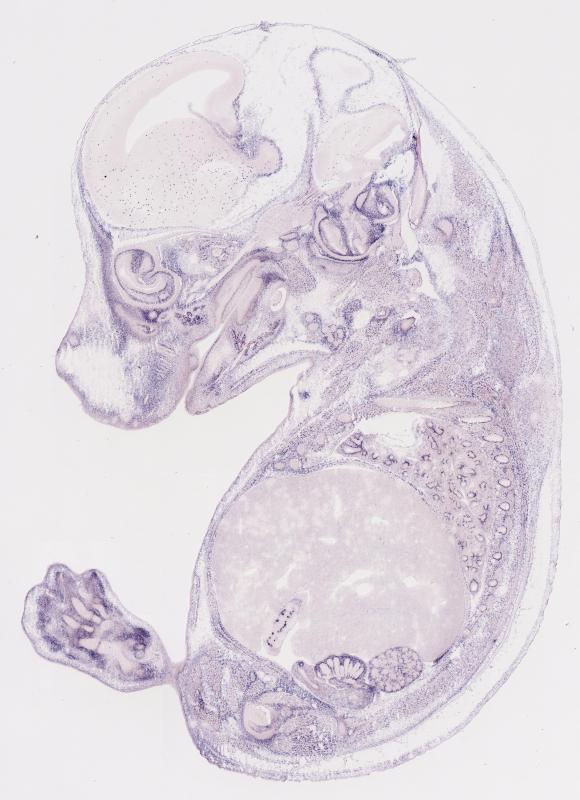

Specimen

MH1215; Specimen C1587:

embryonic day 14.5